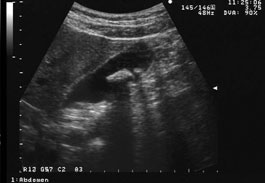

写真は典型的な胆石の超音波像である。胆嚢内にあるのが胆石であることは本例の場合には可動性を確認しなくても診断できる。しかし注意すべきは胆石の後方の胆嚢壁が音響陰影のために観察できていないことである。胆石と判定できても動かせる結石は必ず動かしてその後方の胆嚢壁の観察を怠らないようにする。 |